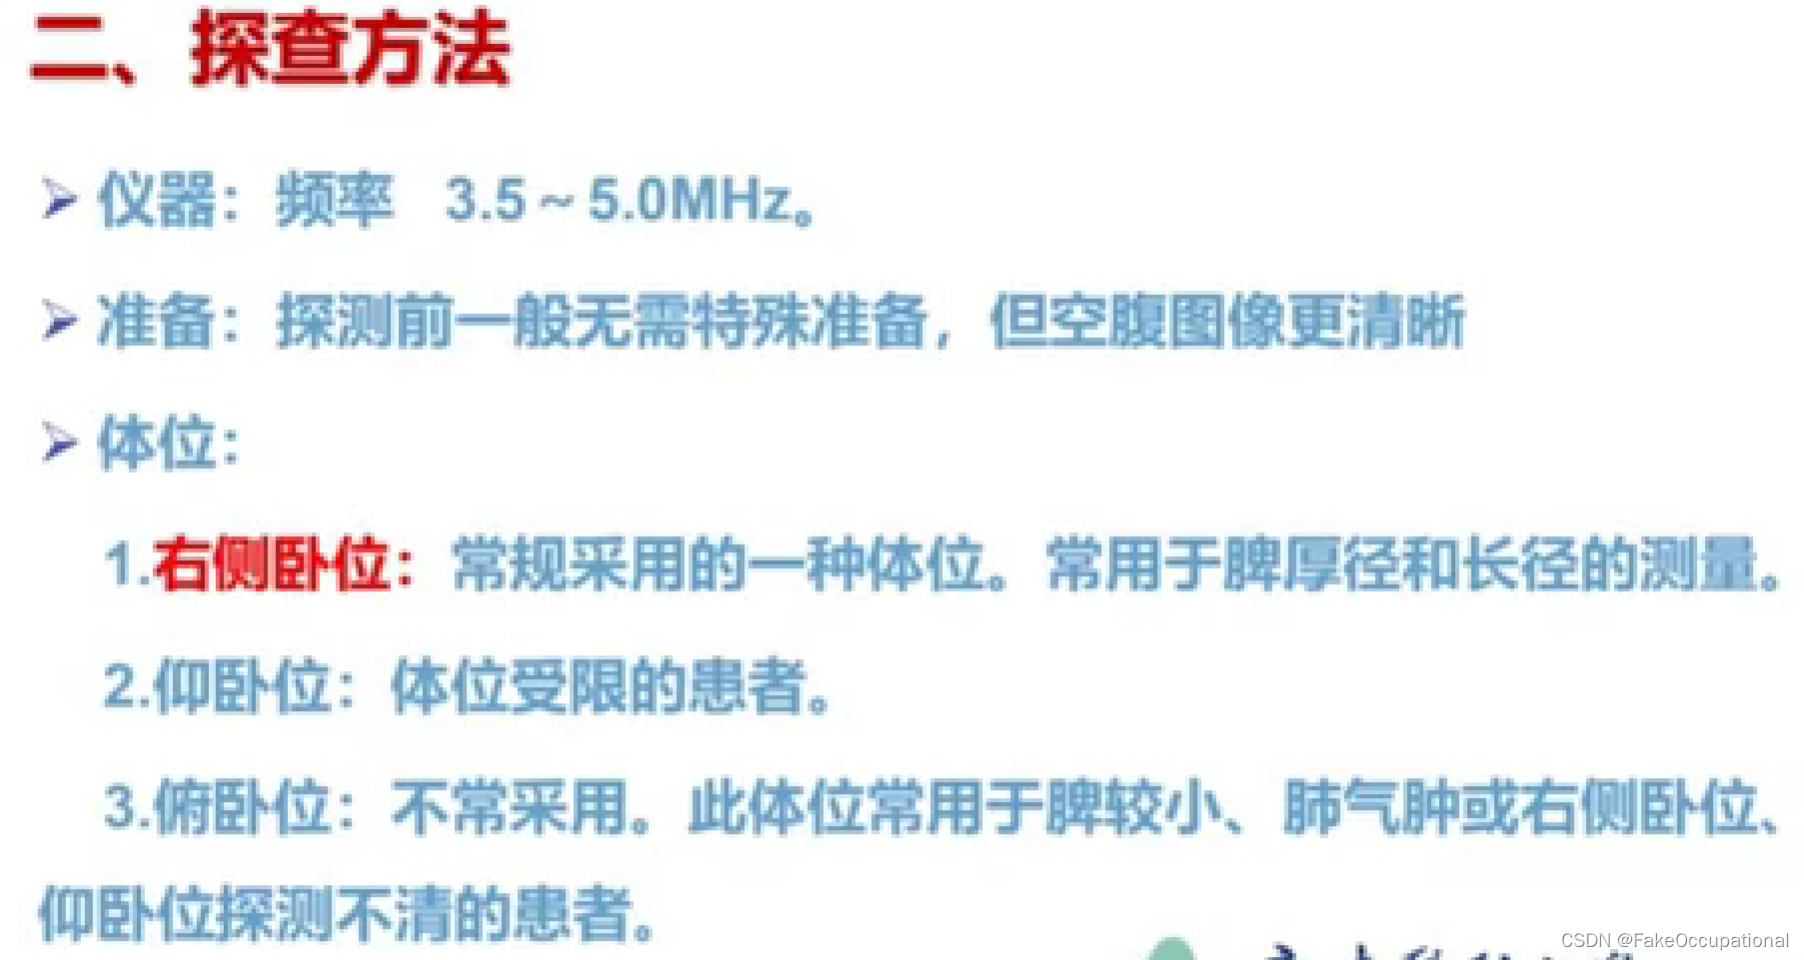

脾脏解剖及正常声像图